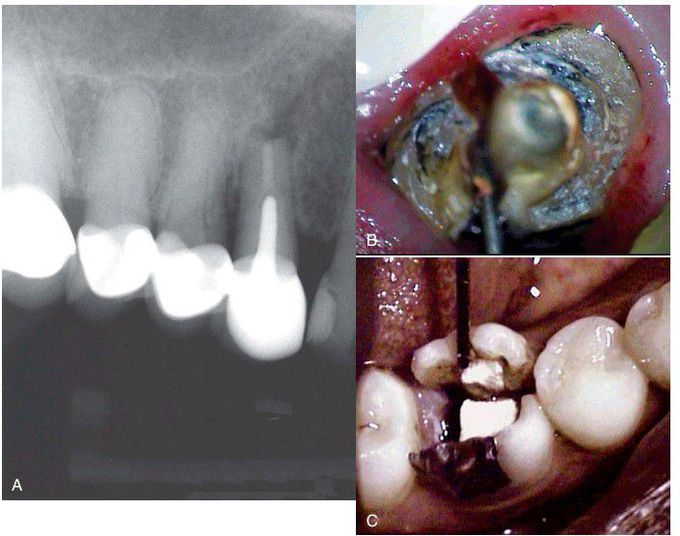

Often it is difficult to diagnose a root fracture unless the coronal restoration is removed. A, This radiograph shows no evidence of a fracture. B, However, once the crown and post are removed, the fracture is easily visualized. C, Sometimes it is helpful to physically push on the axial walls of the clinical crown in order to observe the existence of a fracture.